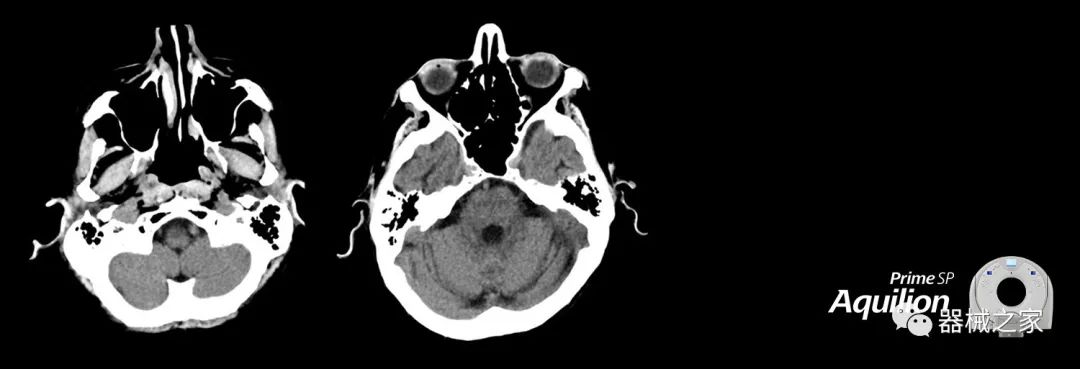

佳能醫(yī)療為Aquilion Prime,Lightning CT系統(tǒng)增加了放射治療套裝

在以患者為中心的放射腫瘤學(xué)領(lǐng)域,計算機斷層掃描(CT)的可訪問性,可重復(fù)性和靈活性至關(guān)重要。為了建立這些價值,佳能醫(yī)療系統(tǒng)美國公司現(xiàn)在正在擴大其放射腫瘤學(xué)CT模擬產(chǎn)品,包括Aquilion Prime SP和Aquilion Lightning 80高級CT系統(tǒng)。除了Aquilion LB之外,Aquilion Prime SP和Aquilion Lightning 80現(xiàn)在還包括放射治療(RT)選項,可為腫瘤學(xué)規(guī)劃提供高質(zhì)量的CT成像和精密工具。

RT套件可在新系統(tǒng)或現(xiàn)有系統(tǒng)上使用,提供經(jīng)濟高效的解決方案,可提高CT掃描儀的使用率,效率和工作流程,包括:

擴展視野(EFOV)可以看到更多的解剖結(jié)構(gòu)。Aquilion LB采用85 cm EFOV,而Aquilion Prime SP和Aquilion Lightning 70采用70 cm EFOV。

RT平臺桌面掃描在同一位置,舒適輕松。

呼吸門控為呼吸運動管理提供強大的靈活性; 和LAP激光器可改善室內(nèi)患者設(shè)置和技術(shù)人員工作流程。

Aquilion Prime SP使設(shè)施能夠處理具有挑戰(zhàn)性的案例,同時為員工提供快速,靈活和高效的解決方案。

佳能醫(yī)療的Aquilion Lightning 80掃描儀還以緊湊,經(jīng)濟的包裝提供高質(zhì)量的成像。Aquilion Lightning 80旨在可靠,高效地運行,在繁忙的環(huán)境中生成高質(zhì)量的圖像。

兩個CT系統(tǒng)均采用0.5 mm x 80排PUREViSION探測器技術(shù)(可配置并從80-160現(xiàn)場升級),78 cm孔徑,50 cm視野,AIDR(自適應(yīng)迭代劑量減少)3-D和SEMAR(單個)能量金屬神器減少)技術(shù)。

Aquilion LB專為滿足腫瘤學(xué)挑戰(zhàn)而設(shè)計,同時優(yōu)先考慮患者護理。Aquilion LB的內(nèi)徑為90 cm,能夠幫助復(fù)雜的患者設(shè)置并提高患者的舒適度。CT模擬定位可以輕松鏡像放射治療定位,更加自信。該系統(tǒng)采用0.5 mm x 16排(32層)PUREViSION探測器技術(shù),70 cm視野,AIDR 3D和SEMAR技術(shù)。